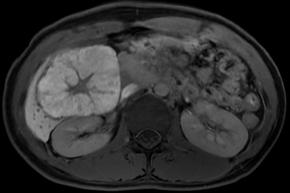

Comments This case report describes a hepatic tumor that was incidentally discovered in a pediatric patient with no underlying liver disease. On color Doppler imaging, there were findings suggestive of a central stellate scar, and the corresponding area demonstrated high signal intensity on T2-weighted MRI. Furthermore, on contrast-enhanced MRI, the lesion, excluding the central scar, showed homogeneous enhancement during the arterial phase and persistent enhancement in the portal venous phase with no evidence of washout. An additional finding, though not presented in the primary text, was homogeneous high signal intensity in the hepatobiliary phase (sparing the central scar). All of these findings are characteristic of focal nodular hyperplasia.

• Hepatobiliary phase image